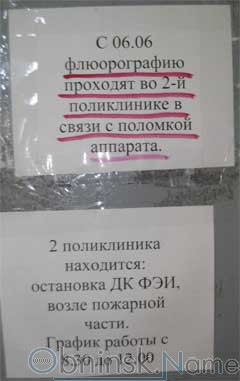

Фотографии рентгеновских снимков без необходимости направления от врача